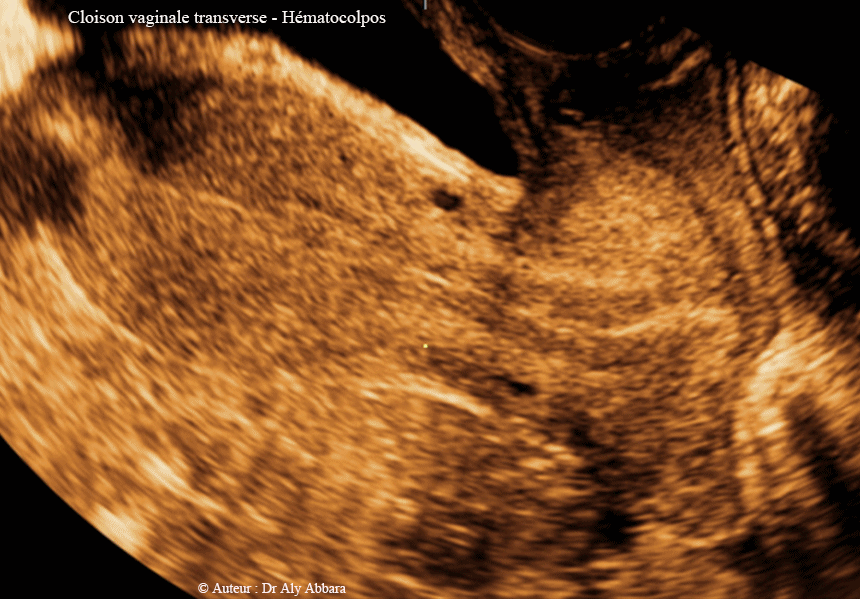

• Images échographiques et cliniques animées mettant en évidence la présence d'une cloison vaginale transversale située au niveau de la jonction du tiers inférieur avec le tiers moyen du vagin.

• Cette cloison vaginale est de 3 à 4 mm d'épaisseur ; elle divise transversalement le vagin en deux compartiments :

• compartiment inférieur, de 3 à 4 cm de long ;

• compartiment supérieur dans lequel s'ébauche l'orifice externe du col utérin. Chez cette patient, ce compartiment est le site d'un hématocolpos par l'accumulation partielle du sang menstruel.

• La cloison vaginale transversale est quasi complète à part la présence d'un pertuis millimétrique dans son centre permettant une évacuation très partielle du sang menstruel vers le vagin bas.

• La patiente est une jeune adolescente de 14 ans se plaignant de dysménorrhée et d'une dyspareunie.